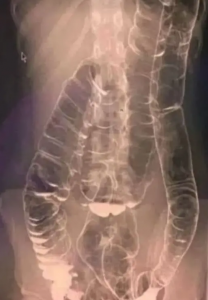

If constipation lasts for a long time, it may slow digestion and cause the colon to stretch, making it harder for the body to pass stool naturally.

Over time, this can lead to issues like abdominal pressure, hemorrhoids, or small tears that cause pain during bowel movements.